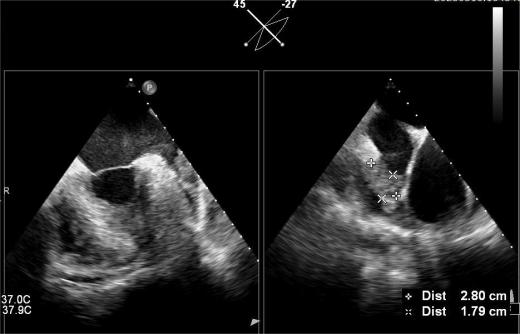

▲血栓位于心耳中段

4.png        5.png

其中首场公开演示的左心耳血栓封堵病例拥有极高难度,患者术前TEE显示左心耳血栓形成伴机化,血栓位于心耳中段,近中端絮状物显著 。封堵机遇只有一次,选型和操作稍有失误,城市增长手术风险 。因而手术采取全麻,并装置了抗栓塞脑动脉;ぷ爸,以削减术中风险 。通过TEE疏导下丈量左心耳大幼以及确认左心耳血栓地位,李岳春教授凭借自身丰硕经验最终决定使用LAmbre 2632型号,选取推送式植入法将左心耳血栓牢牢锁死于远端,并且封堵器一次成型,封堵成效极佳,实现后取出脑;ぷ爸,均未见血栓,顺利实现了此台高难度的手术,获得了学员们的一致认可 。